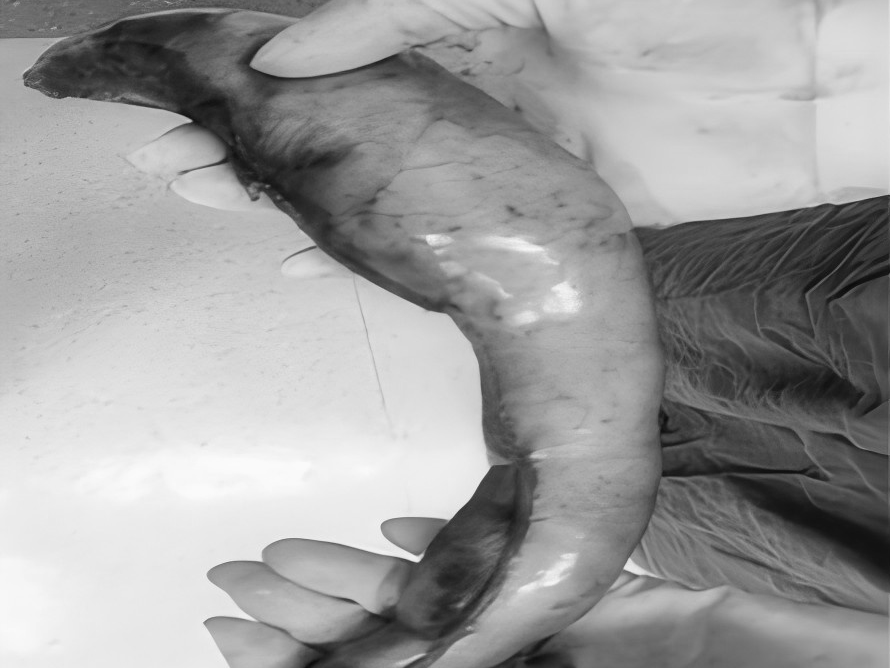

“医生,我爸妈只是关节痛,吃了点止痛药,怎么会胃穿孔要手术?”在普外科病房里,这样的疑问屡见不鲜,很多儿女都困惑不已:明明只是想帮老人缓解疼痛,一片孝心,怎么会把父母送进手术室? 今天,贵州航天医院普外科就来和大家聊聊如何科学、安全地使用止痛药,保护我们脆弱的胃肠,享受健康的生活! 【止痛药咋就把胃吃穿了?】 把胃想象成一个气球,胃黏膜就是内壁,很多止痛药(比如布洛芬、双氯芬酸钠等)会削弱这层内壁,胃酸就像强酸,没了胃黏膜这层内壁保护就会直接腐蚀胃,轻则糜烂、溃疡,重则出血、穿孔。 最危险的是:胃穿孔早期可能只是隐隐作痛、有点胀,容易被当成“老胃病”扛过去,等剧痛发作时,胃里的东西已流进腹腔,危及生命。 【为啥受伤的总是老年人?】 ※胃功能减退:上了年纪,胃黏膜变薄、修复能力下降。 ※多种药同吃:很多老人同时服用降压药、抗凝药,和止痛药叠加,胃根本扛不住。 ※自行用药:怕麻烦不去医院,按老经验或邻居推荐买药,隐患最大。 【安全用药“四要、四不要”】 四要—— ✔要查明原因:疼痛是警报,先看病再吃药,别盲目止痛。 ✔要保护胃:在医生指导下可加用胃黏膜保护剂(如奥美拉唑)。 ✔要饭后吃:务必饭后半小时服用,减少刺激。 ✔要见好就收:不疼了就停药,绝不长期吃。 四不要—— ❌不要自己加量:疼得厉害?找医生,别加药。 ❌不要混着吃:不同止痛药一起吃等于伤害叠加。 ❌不要长期吃:一般疼痛不连续吃超过一周。 ❌不要忽视警报:出现胃部不适、黑便、呕血、剧烈腹痛,立即停药就医! 【对付慢性疼痛,还有其他好办法】 ▶热敷、冷敷:简单有效,很多肌肉关节痛都管用。 ▶理疗、按摩:找正规中医推拿,效果不输止痛药。 ▶温和运动:散步、打太极,增强肌肉力量。 ▶转移注意力:养花、写字、聊天——当你不那么关注“痛”时,痛感往往会减轻。 【给子女的2点提醒】 ※管好药箱:定期清理过期药,搞清楚老人每天在吃什么药。 ※当好翻译:陪老人看病时,说清哪里痛、吃过啥药、效果如何。 止痛药是缓解疼痛的有效工具,但绝非“万能神药”。请一定记住:面对疼痛,“硬扛”不是办法,“乱吃”更是大忌,守护胃肠健康,从科学用药开始。 注:本文仅为健康科普,旨在提高公众用药安全意识,具体用药请务必咨询专业医生,遵医嘱执行。 贵州航天医院普外科专家简介 高大勇 普外科(肛肠外科)学科带头人、名誉主任,主任医师、教授 临床擅长:对中西医结合诊治肛肠学科各种常见病、多发病及疑难杂症等具有丰富的临床经验。 原遵义市第一人民医院(遵义医科大学第三附属医院)、遵义市中医院肛肠科主任。中华中医药学会肛肠分会常委,全国中医肛肠学科名专家,中国健康促进与教育协会肛肠分会常委,中国康复医学会肛肠疾病康复专业委员会常委,中国民间中医医药研究开发协会肛肠分会副秘书长,中国医师协会中西医结合肛肠医师专业委员会常委,国家二级心理咨询师,贵州省第一批中医名医工作指导老师,遵义市名中医,遵义市肛肠学会会长,遵义市肛肠质控中心名誉主任,遵义市中西医结合学会名誉会长,遵义市健康科普专家,原贵州省中西医结合学会肛肠分会副主任委员、贵州省中医肛肠质控中心副主任、遵义市医学会医疗鉴定委员会专家、遵义市卫生系列高评委。发表论文30余篇,主编和参编医学著作5本,主持省级科研课题2项、市级科研课题2项、院级科研课题1项。 梁 跃 普外科党支部书记、主任,主任医师 临床擅长:对普外科各类肿瘤手术具有丰富的临床经验。 毕业于遵义医学院,遵义市医学会小儿外科学分会常务委员,遵义市肛肠协会理事,遵义市医学会核医学分会(第二届)委员会委员;荣获第三期“黔医人才计划”优秀学员称号;主持市级课题1项,完成省级课题1项,在国内各类刊物上发表论文10余篇。 钱科洪 民盟盟员,普外科副主任医师 临床擅长:从事普外科临床工作30余年,对各类普外科疾病的诊治、乳腺、甲状腺、胃十二指肠、结直肠等疾病及疑难杂症具有丰富的临床经验。 毕业于遵义医学院临床医疗系,2009年前往中山大学附属第一医院微创外科进修学习,在国内各专业期刊发表论文数篇。 贵州航天医院普外科简介 基本情况 贵州航天医院普外科成立于1968年,前身属于航天部O61基地3417医院外一科,1998年3417医院、3427医院合并后更名为普外科,下设胃肠外科、肛肠外科2个亚专业科室,拥有在全市较为先进的专科设备和技术,是中国疝病专科联盟单位,贵州医科大学附属医院胃肠外科专科联盟单位。开放床位40张,配备医护人员21人。 专科特色 普外科致力于胃肠及肛肠疾病的外科临床诊治及科研,以腹腔镜微创外科技术为本,形成以快速康复治疗胃肿瘤、结直肠肿瘤、小肠肿瘤、直肠脱垂、肥胖病、急腹症、各类疝、痔、瘘等专科特色,同时注重胃肠疾病尤其是结直肠恶性肿瘤的基础研究和临床转化研究,总体诊断和治疗水平在区域同级医院居于领先水平。 开展手术:腹腔镜下胃癌根治术,腹腔镜下袖状胃切除术,腹腔镜下胃肠道间质瘤切除术,腹腔镜下结、直肠癌根治术,胃癌、结直肠癌的精准治疗,腹腔镜下小儿疝气、成人疝修补术,腹腔镜下阑尾手术,内痔的硬化注射治疗及痔疮的微创治疗:ATH、PPH、TST,直肠脱垂的各种手术治疗,难治性伤口VSD技术,鼻胃肠管、肠梗阻导管置入术,肛肠术后间歇性导尿技术,并引进了中医适宜技术,也为各种化疗患者提供输液港安装,提高患者就医体验。 腹腔镜下腹股沟疝 无张力修补术 腹股沟疝里金斯坦 (Lichtenstein)手术 PPH微创术治疗环状混合痔 黏连性或炎性肠梗阻-肠梗阻导管 腹腔镜袖状胃切除 腹腔镜阑尾切除术 腹腔镜阑尾肿瘤切除术 腹腔镜下结肠癌根治术 诊疗范围 胃肿瘤、结直肠肿瘤、小肠肿瘤、肥胖症、各类急腹症、腹部外伤、腹壁疝、便秘、直肠脱垂、痔疮、肛瘘、肛裂等胃肠、肛肠外科疾病。 END